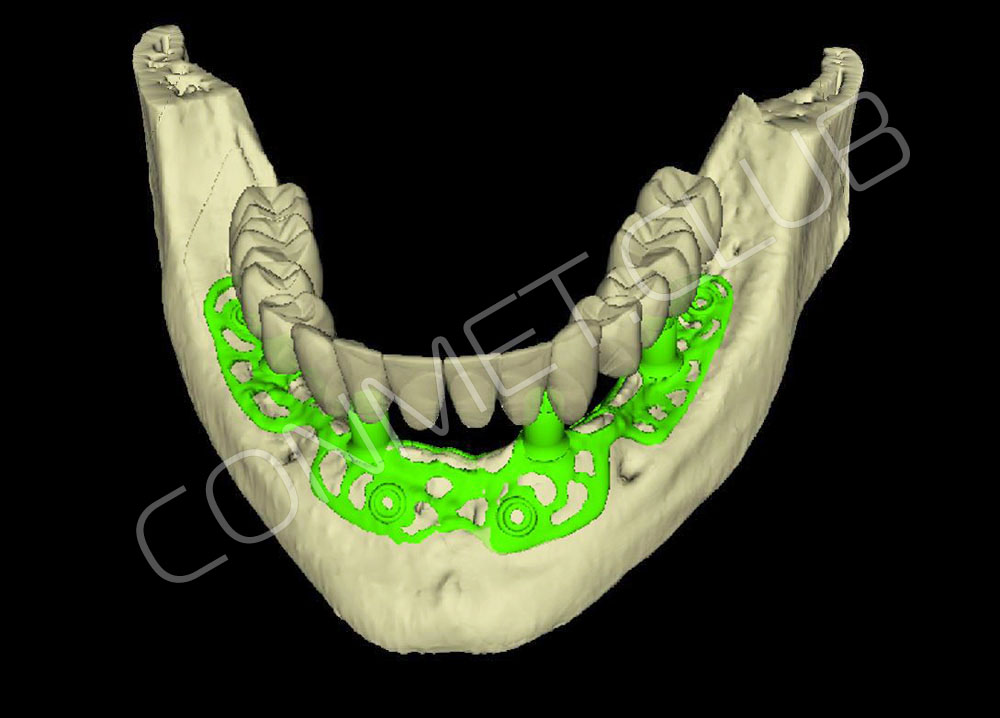

2. После этого произвели компьютерное моделирование самого имплантата и фиксирующих элементов. Примечательно, что в абатментах, использовался отлично зарекомендовавший себя и проверенный десятилетиями интерфейс КОНМЕТ! В результате получили несколько специальных файлов, позволяющих не только сделать сам имлантат, но еще до операции изготовить и сами зубы. Данные файлы передали в изготовление на специальном 3D оборудовании.

Посмотрите на небольшом клиническом примере новый подход к конструированию имплантата по сравнению с имплантатами описанными в начале этой статьи.

Для просмотра проведите курсором мыши по изображению имплантата